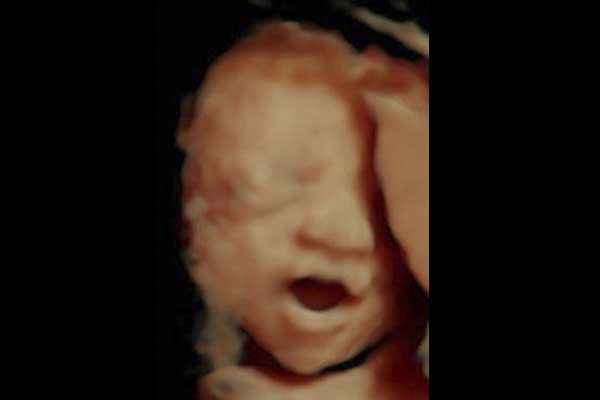

Ecografias en 4d

Reconstrucción Digital 3d en tiempo real, visualización de los movimientos fetales, bostezos, sonrisas, etc.

ECOGRAFIA 4D

Nuestros estudios lo confirman, Ecografías 3D y 4D Manizales Pereira

El ultrasonido en 4D es una ecografia 3D con movimiento, en tiempo real.

En cualquier momento,pero la solicitan mas entre los 6 y 8 meses ( 26 y 34 semanas ).

Sin duda alguna! es una de las experiencias más emocionantes del embarazo y es maravilloso poderlo compartir con quien tú quieras.